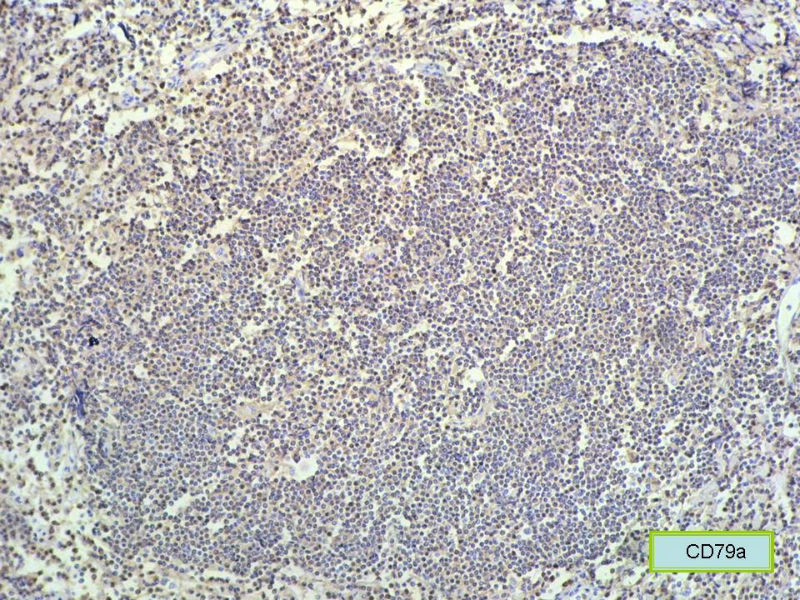

赞成以上专家的讨论,根绝病史,HE形态考虑小细胞病变,CD3、CD5散在+,还是倾向淋巴造血系统病变,CD20、CD79a阳性不明确,可以考虑复查,加做PAX-5,核阳性容易判断,另再加做鉴别其它小细胞肿瘤的抗体:CD99、CD43、CyclinD1、CK、CgA、Syn等,了解病史:骨髓、末梢血、肝、脾等。

请再标记CD20和CD79a!图片中阳性不明确,根据T细胞标记看,应该是B细胞结节。Ki67散而少,不支持低级别滤泡性淋巴瘤,若B细胞弥漫阳性,则是惰性B细胞非霍奇金淋巴瘤,首先考虑套细胞,然后是边缘区淋巴瘤。不做生发中心标记,Bcl-2在小B细胞淋巴瘤分类中无意义。

本例是发生在特殊部位“结膜下”,HE肿瘤细胞形态形态一致,形似单核样B细胞。B细胞标记若明确阳性,诊断MALT是挺合理的。

CD20(+),Kappa(+),ki-67(+)>2%,Lambda(+),Pax-5(+),符合粘膜相关淋巴瘤。